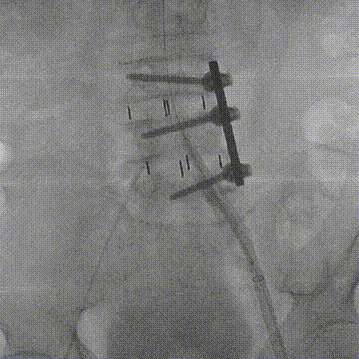

手术过程

入路造影显示左髂总动脉-左股总动脉严重狭窄伴钙化

边打造影剂边缓慢撤20F沛嘉大鞘,发现血管夹层

沿导丝送入10mm×100mm覆膜支架至左髂动脉-股总动脉

复查下肢造影显示右髂总动脉-右股总动脉明显狭窄